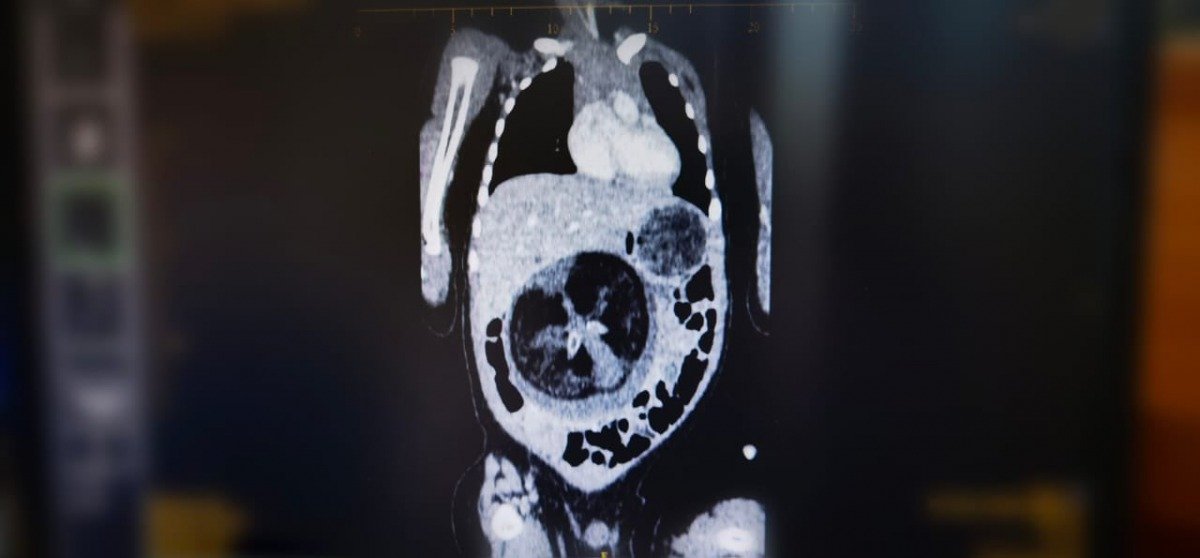

أفادت وكالة الأنباء العمانية، بأن قسم جراحة الأطفال بالمستشفى السلطاني في البلاد، أجرى عملية جراحية نادرة تمثلت في استئصال جنين من داخل جنين.

وأشارت الوكالة إلى أن العملية الجراحية التي جرت عبارة عن استئصال جنين من داخل جنين، لطفل يبلغ من العمر ثمانية أشهر.

كما نشرت صورا في “تويتر” أظهرت الصور الصوتية للجنين، وللحالة التي تمت معالجتها، وفريق طبي مختص.

يُذكر أن هذه الظاهرة الطبية تعرف ب” Fetus in feto” وتحدث بنسبة 1 من كل 500 ألف حالة ولادة حية على مستوى العالم.